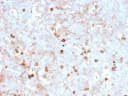

Anti-CD14 (Monocyte / Macrophage Marker)(rLPSR/2408)

Recognizes a protein of 55 kDa, identified as CD14 (also known lipopolysaccharide receptor). CD14 is expressed strongly on monocytes and macrophage and weakly on the surface of neutrophils. CD14 is anchored to cells by linkage to glycosylphosphatidylinositol (GPI) and functions as a high affinity receptor for complexes of LPS and LPS binding protein (LBP). Soluble CD14, also binding to LPS, acts at physiological concentration as an LPS agonist and has, at higher concentrations, an LPS antagonizing effect in cell activation. Primary antibodies are available purified, or with a selection of fluorescent CF® Dyes and other labels. CF® Dyes offer exceptional brightness and photostability. Note: Conjugates of blue fluorescent dyes like CF®405S and CF®405M are not recommended for detecting low abundance targets, because blue dyes have lower fluorescence and can give higher non-specific background than other dye colors.Synonyms:

IHC, FFPE (verified)Validated Applications:

IHC, FFPEPositive Control:

A549, THP-1 cells and human monocytes. Lymph nodes and tonsils.Concentration: